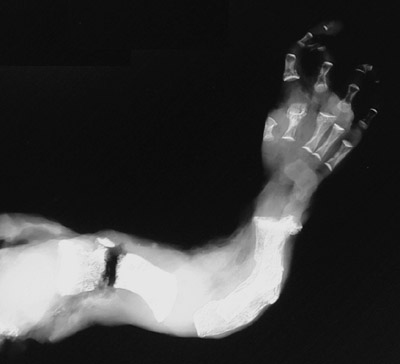

The bones of this fetal extremity demonstrate recent and remote fractures in a case of the lethal perinatal form of osteogenesis imperfecta.